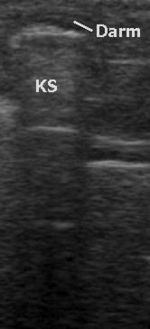

B-Mode (B für englisch brightness modulation) ist eine andere Darstellung der Information des Amplituden-Modus, bei der die Echointensität in eine Helligkeit umgesetzt wird. Durch mechanisches Bewegen der Sonde überstreicht der Messstrahl eine Fläche in einer Ebene ungefähr senkrecht zur Körperoberfläche. Der Grauwert eines Bildpunktes auf dem Bildschirm ist ein Maß für die Amplitude eines Echos an dieser Stelle.

2D-Echtzeitmodus (2D-realtime)

Im 2D-Echtzeitmodus, der derzeit häufigsten Anwendung des Ultraschalls, wird ein zweidimensionales Schnittbild des untersuchten Gewebes durch automatische Verschwenkung des Messstrahls und Synchronisierung der B-mode- Darstellung in Echtzeit erzeugt. Das Schnittbild wird dabei aus einzelnen Linien zusammengesetzt, wobei für jede Linie ein Strahl ausgesendet und empfangen werden muss. Die Form des erzeugten Bildes hängt dabei vom eingesetzten Sondentyp ab. Der 2D-Echtzeitmodus kann mit anderen Verfahren wie dem M-Mode oder der Doppler-Sonografie gekoppelt werden. Je nach Eindringtiefe und Sondentyp können nur einige wenige oder bis zu über hundert zweidimensionale Bilder pro Sekunde dargestellt werden.